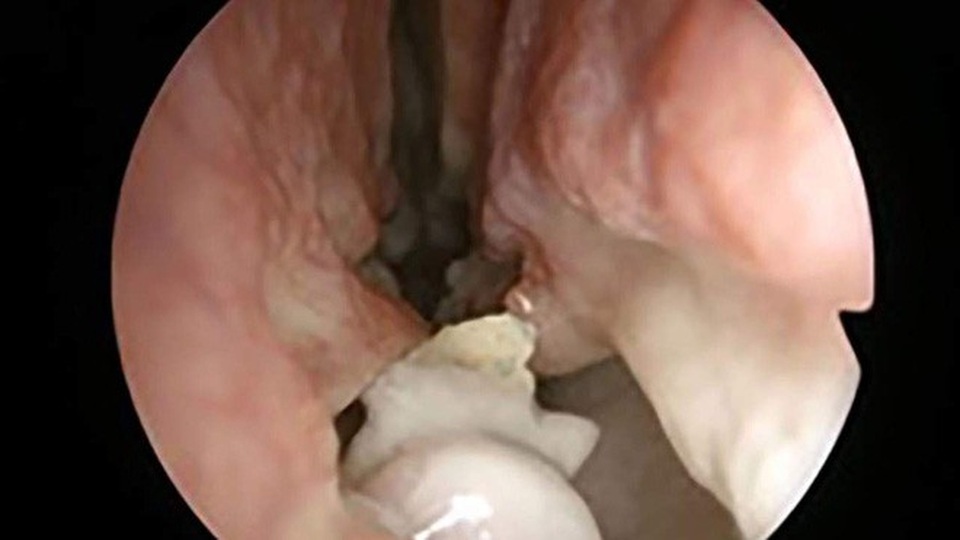

Tuy nhiên, sau khi chụp X-quang thì “danh tính” của thủ phạm chính gây ra hiện tượng trên mới được phát hiện, đó là một dị vật trắng, có lông ở khoang mũi.

Ban đầu, các bác sỹ nghi ngờ rằng đây là một khối u nang có hình dạng lạ với một số đặc điểm dị thường khác, nên đã tiến hành làm phẫu thuật cắt bỏ. Thật bất ngờ, vì sau đó họ mới nhận ra không có một khối u nào cả mà đó là một chiếc răng mọc sai chỗ.